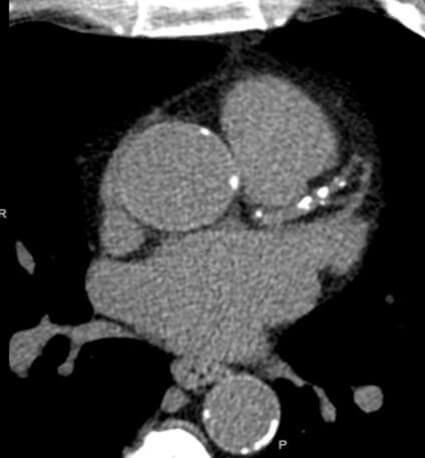

CAC Scan